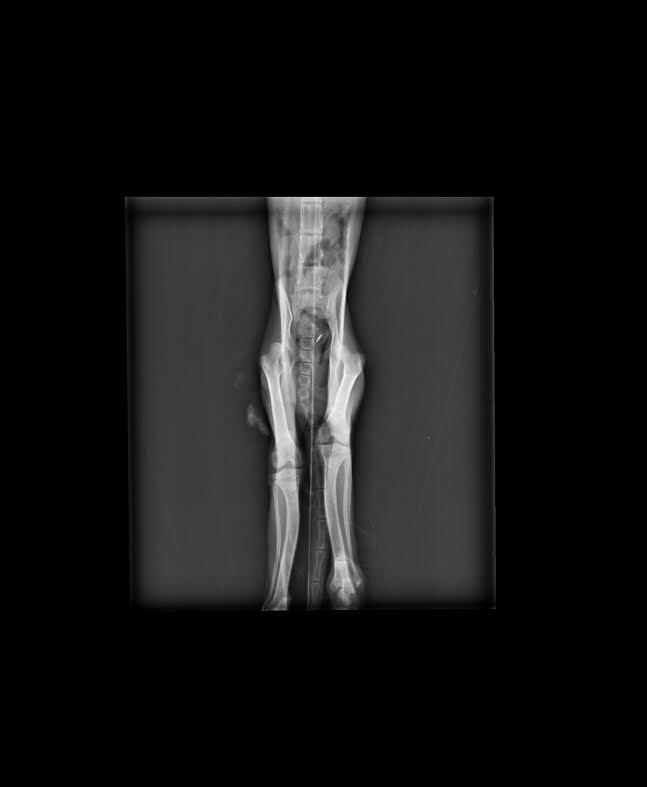

毛髮雜亂,有輕癱.血尿.虛弱.前肢脘關節脫臼.右側腸薦關節脫位 .右側髖關節脫位,

其實醫生說了那摸多很艱深的疾病,

在X光下說明了一切...

因為四肢有三肢都缺少一塊骨頭...

這不是後天造成是先生的...

4.X-ray 400*3